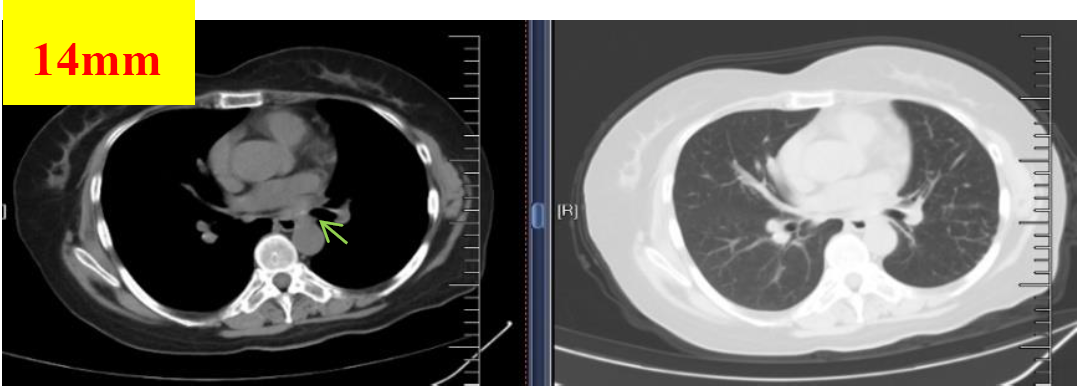

图3 2018.08.28影像学检查(PR)

图4 2018.09.27影像学检查(PR)